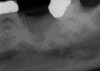

Fig 20. (Case 4) Radiograph of tooth No. 30, which had a hopeless prognosis.

Figure 20

Fig 21. Radiograph of extraction socket. Buccal plate was two-thirds resorbed.

Figure 21